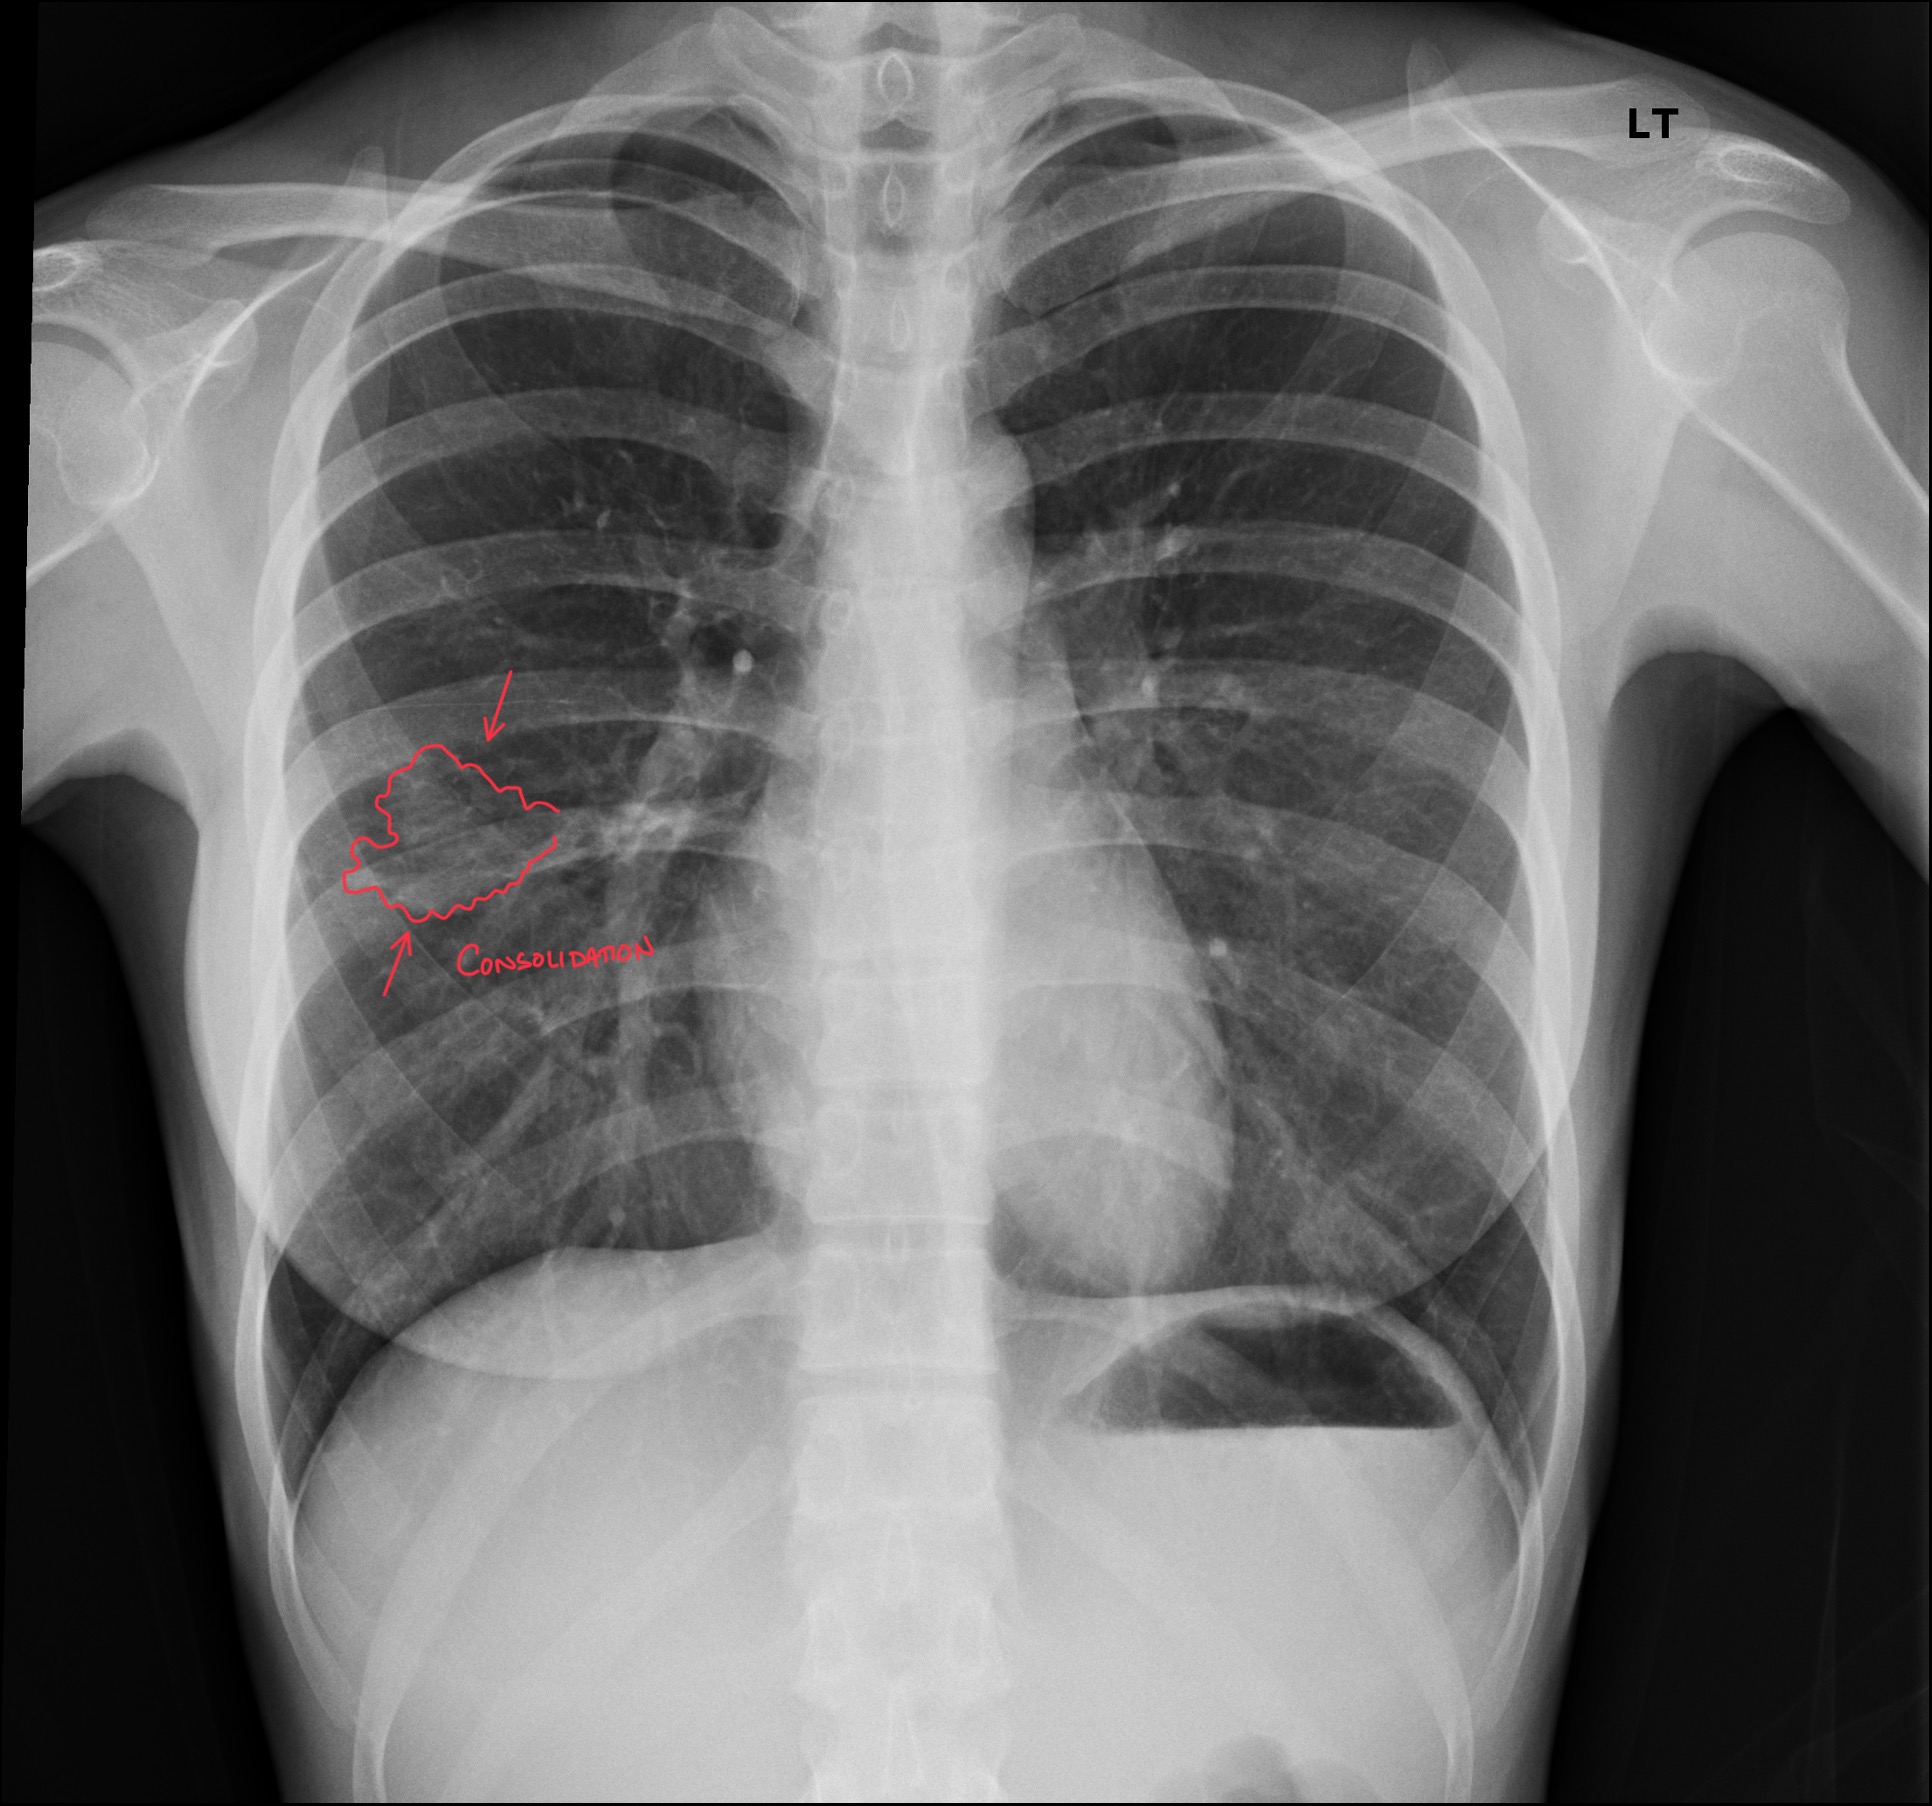

DACBR Report: Second Opinion on Right Mid-Lung Field Pneumonia in a 30-Year-Old Female with Cough

DACBR Report: Second Opinion on Right Mid-Lung Field Pneumonia in a 30-Year-Old Female with Cough Overview Right mid-lung field pneumonia